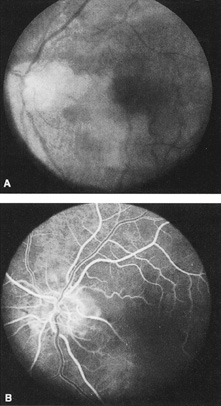

The clinical picture is typically striking. Patients present with a sudden painless loss of vision. The appearance of a cherry-red spot in the fundus is characteristic (Fig. 1).2 The cherry-red spot appears because soon after obstruction of the blood flow to the inner retina, the normally transparent retina becomes opaque and blocks the brownish-red color from the underlying choroid, which is still supplied by blood. Because the retina overlying the foveola is relatively thin, however, the normal color of the choroid is still visible in this area.3,4 Although characteristic, the cherry-red spot is not pathognomonic for central retina artery obstruction.5 Sometimes the characteristic cherry-red spot does not develop; there may be only a slight accentuation of the brownish-red color in the foveola.4 It is not known how long it takes this cherry-red spot to appear, but in a primate model, it has appeared as early as 30 minutes after obstruction.6 An afferent pupil defect is usually present.2

Fig. 1. A: Acute central retinal artery obstruction with a cherry-red spot. B and C: Intravenous fluorescein angiography. There is a delay of dye appearance in the central retinal artery, and when it does appear, it does not fill the arteries completely. D: Ocular coherence tomography (OCT) at the time of occlusion showing the increase in retinal thickness and reflectivity of the inner layers of the retina. E: Seven months later there is significant optic atrophy(G), and the OCT (F) shown now has marked thinning of the retina.

With time, the retinal opacity diminishes, generally leaving an optic nerve that is atrophic (Fig. 1). Frequently, thinned retinal arteries and veins also remain.7,8 No foveolar light reflex is evident, and a finely pigmented appearance of the macula is typical.7 In some cases, arterial collaterals develop at the optic disc.9–11 Rarely, anatomoses that exist between the central retinal artery and the ciliary arteries become visible as preretinal loops (Nettleship collaterals) after an occlusion at the edge of the disc.12,13,378In approximately 20% of patients, an embolus is evident somewhere in the arterial system.14 Emboli are discussed later.

Intravenous fluorescein angiography is useful in showing the details of the abnormal circulation of a central retinal artery obstruction (Fig. 1). The principal abnormality is the delay in the appearance of the dye in the central retinal artery and its branches.2 Rather than the central retinal artery and its branches filling rapidly, considerable time may elapse before the entire arterial system is filled.15 The filling of the retinal arteries is often abnormal, with the fluorescein partially filling an artery (a dye front) or hugging the vessel wall, as in normal venous filling.15

Optic coherence tomography (OCT) of an acute central retinal artery occlusion shows a slight increase in the thickening of the retina and reflectivity of the inner layers of the retina that correspond to the opacity seen clinically (Fig. 1).409 With time, the disc becomes atrophic and the retina thinner.